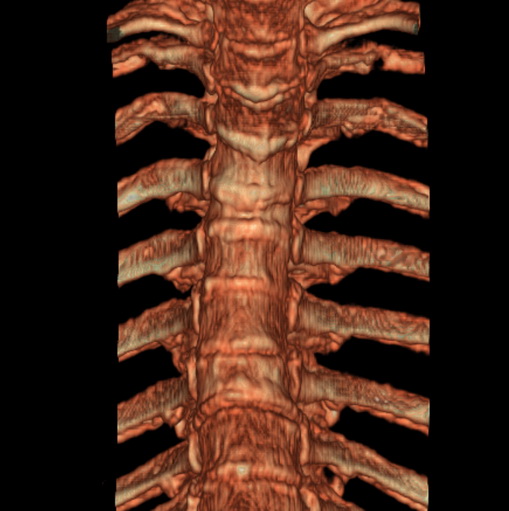

标题: CT25377:脊柱有无压缩骨折?

女、73、胸痛、胸闷3个月,无明显外伤病史,x线疑t4、t7陈旧压缩骨折,ct未经明显骨折,请问结论如何报?

老年女性病人,骨质稀疏,有些驼背,t4明显变扁,t7略变扁,椎体边缘无中断,骨小梁排列正常,无嵌插所致致密线。结合无明显外伤史,考虑老年骨质稀疏,慢性压缩改变,正如老年人骨质稀疏椎体呈双凹改变一样。我考虑报:老年骨质稀疏,t4、t7楔形变,脊柱曲度改变(驼背).敬请大家指教。